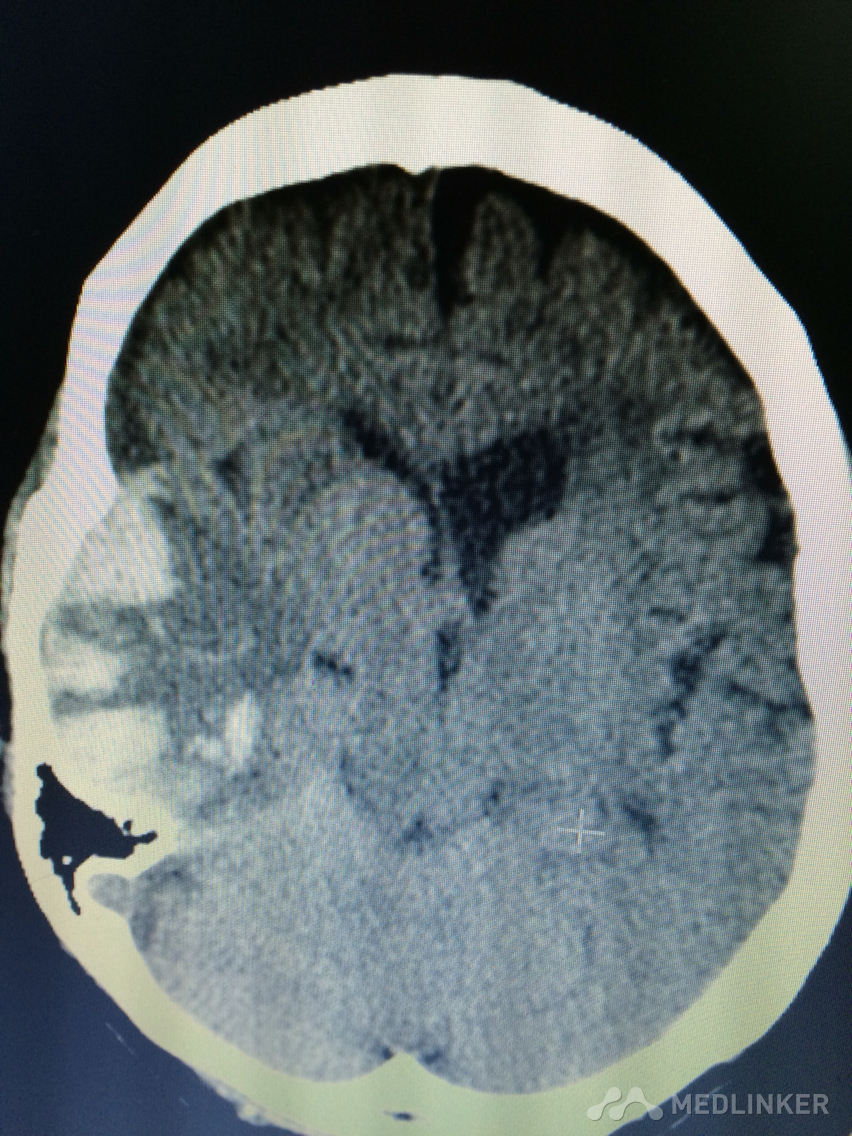

下面的CT考虑?

1天前,患者睡醒后出现反应迟钝,认知功能障碍,左侧肢体乏力。 既往无高血压病史,近期无外伤史。